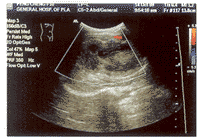

儿童肝脏巨大炎性假瘤1例

患者, 女, 10岁, 腹痛,发现上腹包块20天, 包块渐增大, 近3日出现消化道症状, 体温升高1周,最高达39.5℃ ......